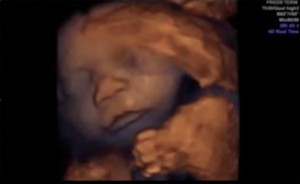

Un estudio desarrollado por el Instituto Marqués de Barcelona nos sorprende revelando que los fetos oyen desde la 16 semana del embarazo y que los sonidos que escuchan son recibidos como una serie de susurros distorsionados. Este instituto ha dado con la clave para que los fetos escuchen música de forma similar a como lo hacemos nosotros, con la misma intensidad y sin que se produzcan distorsiones, escuchando la música por vía vaginal.En el vídeo que encabeza el post podéis ver la expresión facial fetal en respuesta a la emisión de música intravaginal, título del trabajo publicado por el Instituto Marqués en la revista científica Ultrasound. Según los resultados obtenidos en la investigación, el feto reacciona ante lo que escucha moviendo la boca y la lengua como si quisiera cantar, evidentemente no, pero es una respuesta al estímulo que está recibiendo que induce a pensar que se trata de una respuesta de movimientos de vocalización.

El estudio tenía como objetivo incrementar la intensidad del sonido que recibía un feto, usando un dispositivo diseñado específicamente para emitir música a través de la vagina materna. Participaron en la investigación varias mujeres embarazadas de entre 14 y 39 semanas, los expertos monitorizaron a los fetos para comprobar sus reacciones al emitir música a través del abdomen y a través del nuevo dispositivo colocado en la vagina, se utilizó música clásica de Johann Sebastian Bach. En las ecografías previas al experimento se observó que un 45% de los fetos realizaba movimientos espontáneos de cabeza y extremidades, un 30% movimientos de la boca o lengua, y un 10% sacaba la lengua, movimientos habituales en un feto despierto.

Con el nuevo dispositivo, el 87% de los fetos reaccionaron con movimientos de la cabeza y extremidades, y movimientos específicos de la boca y la lengua que cesaban cuando dejaban de escuchar la música, lo que delataba claramente que reaccionaban a lo que escuchaban. Los expertos apuntan que un dato llamativo era que el 50% de los fetos reaccionaron ante la música abriendo mucho las mandíbulas y sacando al máximo la lengua. Hay que decir que con los dispositivos musicales que se colocan en el abdomen, con una intensidad de sonido de 98,6 decibelios (bastante elevado) no se produjeron cambios en las expresiones faciales de los fetos.